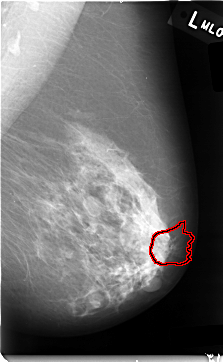

C_0006_1.RIGHT_MLO

FILE: C_0006_1.LEFT_MLO.OVERLAY

TOTAL_ABNORMALITIES 1

ABNORMALITY 1

LESION_TYPE MASS SHAPE ARCHITECTURAL_DISTORTION MARGINS N/A

ASSESSMENT 4

SUBTLETY 1

PATHOLOGY MALIGNANT

TOTAL_OUTLINES 1

BOUNDARY